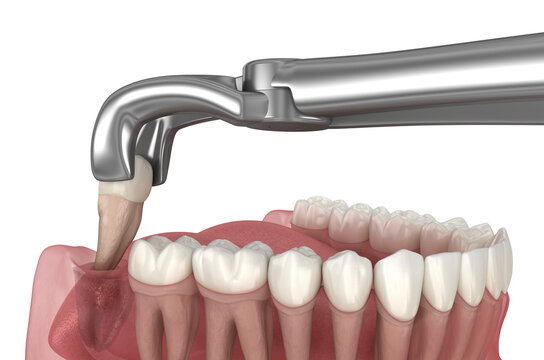

Experiencing severe tooth pain that won’t go away? It could be a sign that your tooth is beyond repair and needs an emergency extraction. When a tooth is severely damaged due to decay, infection, or trauma, removing it may be the best option to prevent further complications.

Delaying treatment can lead to worsening pain, gum infections, and the spread of bacteria to other teeth. Our skilled emergency dentists in Wood Dale provide safe, efficient tooth extractions with minimal discomfort. We offer same-day emergency appointments to address urgent dental issues quickly and effectively.

After an extraction, we provide personalized tooth replacement options, including dental implants and bridges, to restore your smile. Protect your oral health and avoid unnecessary pain—schedule an emergency dental visit today. Call our Wood Dale emergency dental clinic now for expert care and immediate relief!